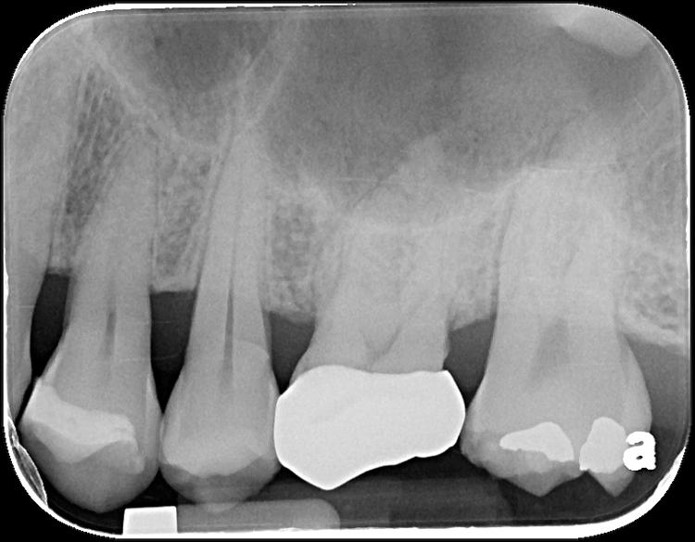

治療前,左上第二大臼齒二次蛀牙

左上第二大臼齒二次蛀牙